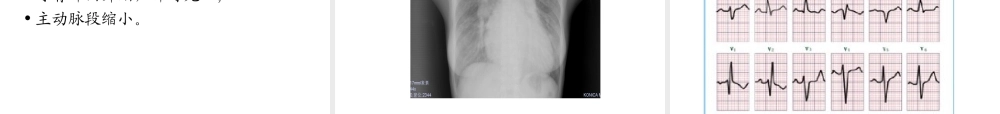

浅谈先天性心脏病武汉亚洲心脏病医院ICU郑萍心脏的胚胎发育关键时期是妊娠后2—8周第2周开始形成第4周开始有循环作用第8周房室间隔长成胎儿血液循环•正常的胎儿血液循环1.通过脐血管与胎盘和母体之间通过弥散方式进行物质(氧气和营养物质)交换2.胎儿循环中只有脐静脉是氧合血3.卵圆孔和动脉导管是正常胎儿血液循环的通路4.左右心室都向全身供血5.体循环为主,虽有肺循环存在,但无气体交换6.供应脑心肝及上肢的血氧含量远远大于下半身2、胎儿血液循环的特点3、出生后的改变•脐带结扎•肺循环形成•卵圆孔关闭•动脉导管关闭先天性心脏病分类(一)左向右分流的先天性心脏病房间隔缺损、室间隔缺损、动脉导管未闭右向左分流的先天性心脏病法洛氏四联症、右室双出口无分流的先天性心脏病肺动脉瓣狭窄、主动脉弓缩窄先天性心脏病分类(二)•非紫绀型房间隔缺损室间隔缺损动脉导管未闭心内膜垫缺损主动脉弓缩窄•紫绀型法乐氏四联症右室双出口肺动脉闭锁完全肺静脉异位引流完全性大动脉转位病因•内因:与遗传有关(染色体畸变)•外因:1)较重要的为宫内感染2)孕母接触大剂量的放射线,缺乏叶酸3)代谢性疾病(糖尿病、高钙血症)4)药物影响(抗癌药、甲糖宁等)5)子宫缺氧(慢性子宫内膜炎)先天性心脏病的治疗方法先天性先天性心脏病心脏病内科内科介入介入治疗治疗外科手术外科手术治疗治疗先天性心脏病的治疗方法内科治疗内科治疗外科治疗外科治疗介入治疗介入治疗1.心衰的治疗2.维持动脉导管的开放3.感染的控制4.其他1.姑息手术2.矫治手术1.ASD封堵2.PDA封堵3.VSD封堵4.PS扩张内外科联合治疗(Hybrid)房间隔缺损•概述•分型•病理生理•临床表现•并发症•X线检查•心电图•超声心动图•心导管检查•治疗•房缺的特征性表现Atrialseptaldefect,ASD一、概述•发病约占先心病总数的5—10%•女性较多见,男:女为1:2•症状较轻二、分型:根据胚胎发生•原发孔型也称为第一孔型房间隔缺损,缺损位于心内膜垫与房间隔交接处•继发孔型最为常见,缺损位于房间隔中心卵圆窝部位,亦称为中央型•静脉窦型分上腔型和下腔型•冠状静脉窦型缺损位于冠状静脉窦上端与左心房间中央型:约占76%下腔型:约占12%上腔型:约占3.5%房间隔缺损分型三、病理生理病生特点•心房水平的左向右分流•分流量与缺损大小、两侧心房压力差及心室的顺应性有关•由于右心血流量增加,舒张期负荷加重,故右心房、右心室增大•艾森曼格(Eisenme...